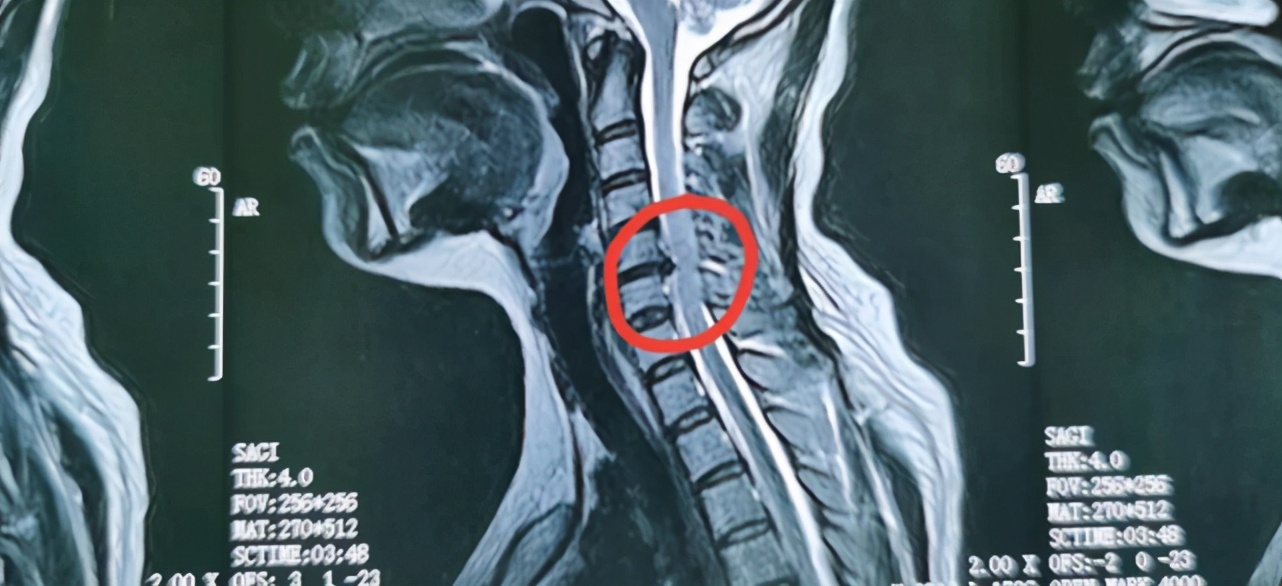

我们再来看吴女士的磁共振成像(MRI)

从吴女士的磁共振成像可以看出, 我标注的红圈里,突出的椎间盘压迫神经通路,形成了一个三角形的小缺口, 正是因为这个小缺口的存在,才导致了吴女士出现各种症状,包括手麻,头晕,甚至心悸的症状。

低温等离子消融术就是要消掉部分的突出,使椎间盘突出整体回缩,保证椎间盘和神经之间有一定的空隙,保证神经通路的通畅。